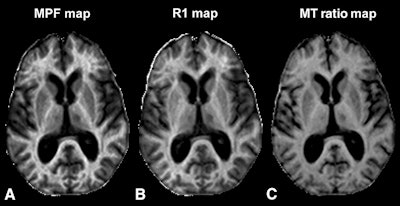

Images show axial sections of 3D MPF, relaxation rate (R1), and magnetization transfer (MT) ratio parametric maps from a 63-year-old woman with secondary-progressive MS. The 3D MPF maps were reconstructed from MT-weighted images and R1 maps. MPF outperforms MT ratio and R1 in detecting MS-related tissue changes. Images courtesy of Radiology.While white-matter MPF had a weaker connection to clinical disability than MPF in gray matter, white-matter MPF was better at discriminating between the relapsing-remitting MS patients and the healthy control subjects.